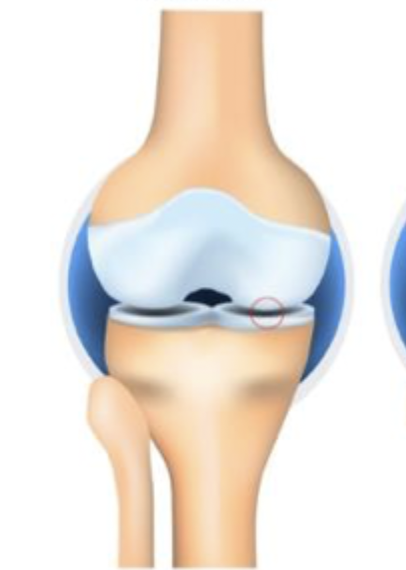

Grade 0

Which stage of OA is characterized by NO joint space narrowing (JSN)